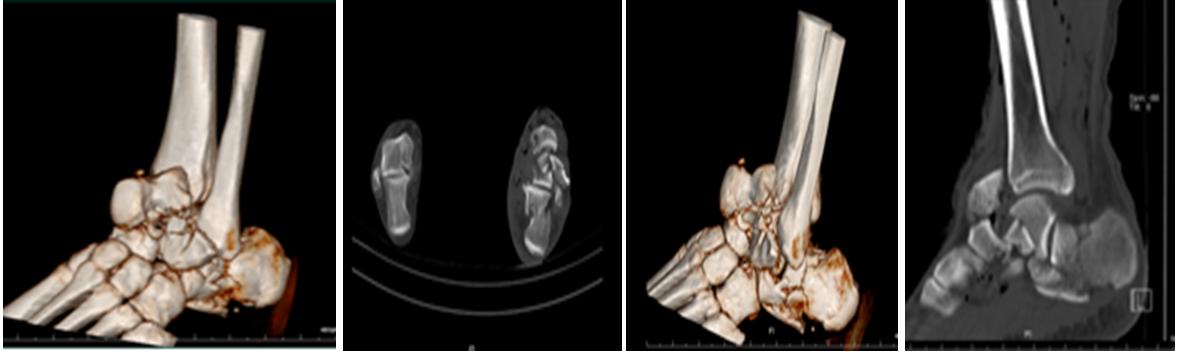

2、CT检查:CT可以360度无死角地看清楚每一块骨头的形态及受伤情况,如果是骨裂,在X线不能确诊时,CT检查就展现出它的优势,比如下图,就是CT的情况,比X线更立体,看的更详尽。